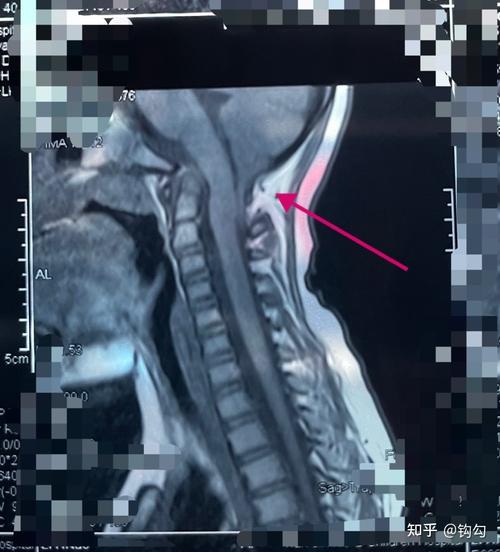

椎间盘突出示意图 轻度膨出时表现为椎间盘后缘正常肾形凹陷

ct检查显示单纯"腰椎间盘突出",这并不是病!盲目治疗不可取